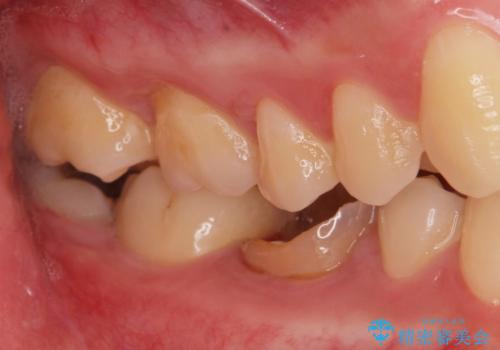

- 古い被せ物が取れたとの事で来院。

過去に根管治療がされている歯でしたが、現在症状はなく、レントゲンでも根尖病巣がないが根尖まで薬が到達していない状態でした。

そのまま被せ物だけやりかえるか根尖病巣の再発のリスクを考えて再根管治療を行うか患者様に決めて頂きました。

被せ物だけの治療を選択されましたのでジルコニアクラウンでの治療を行いました。